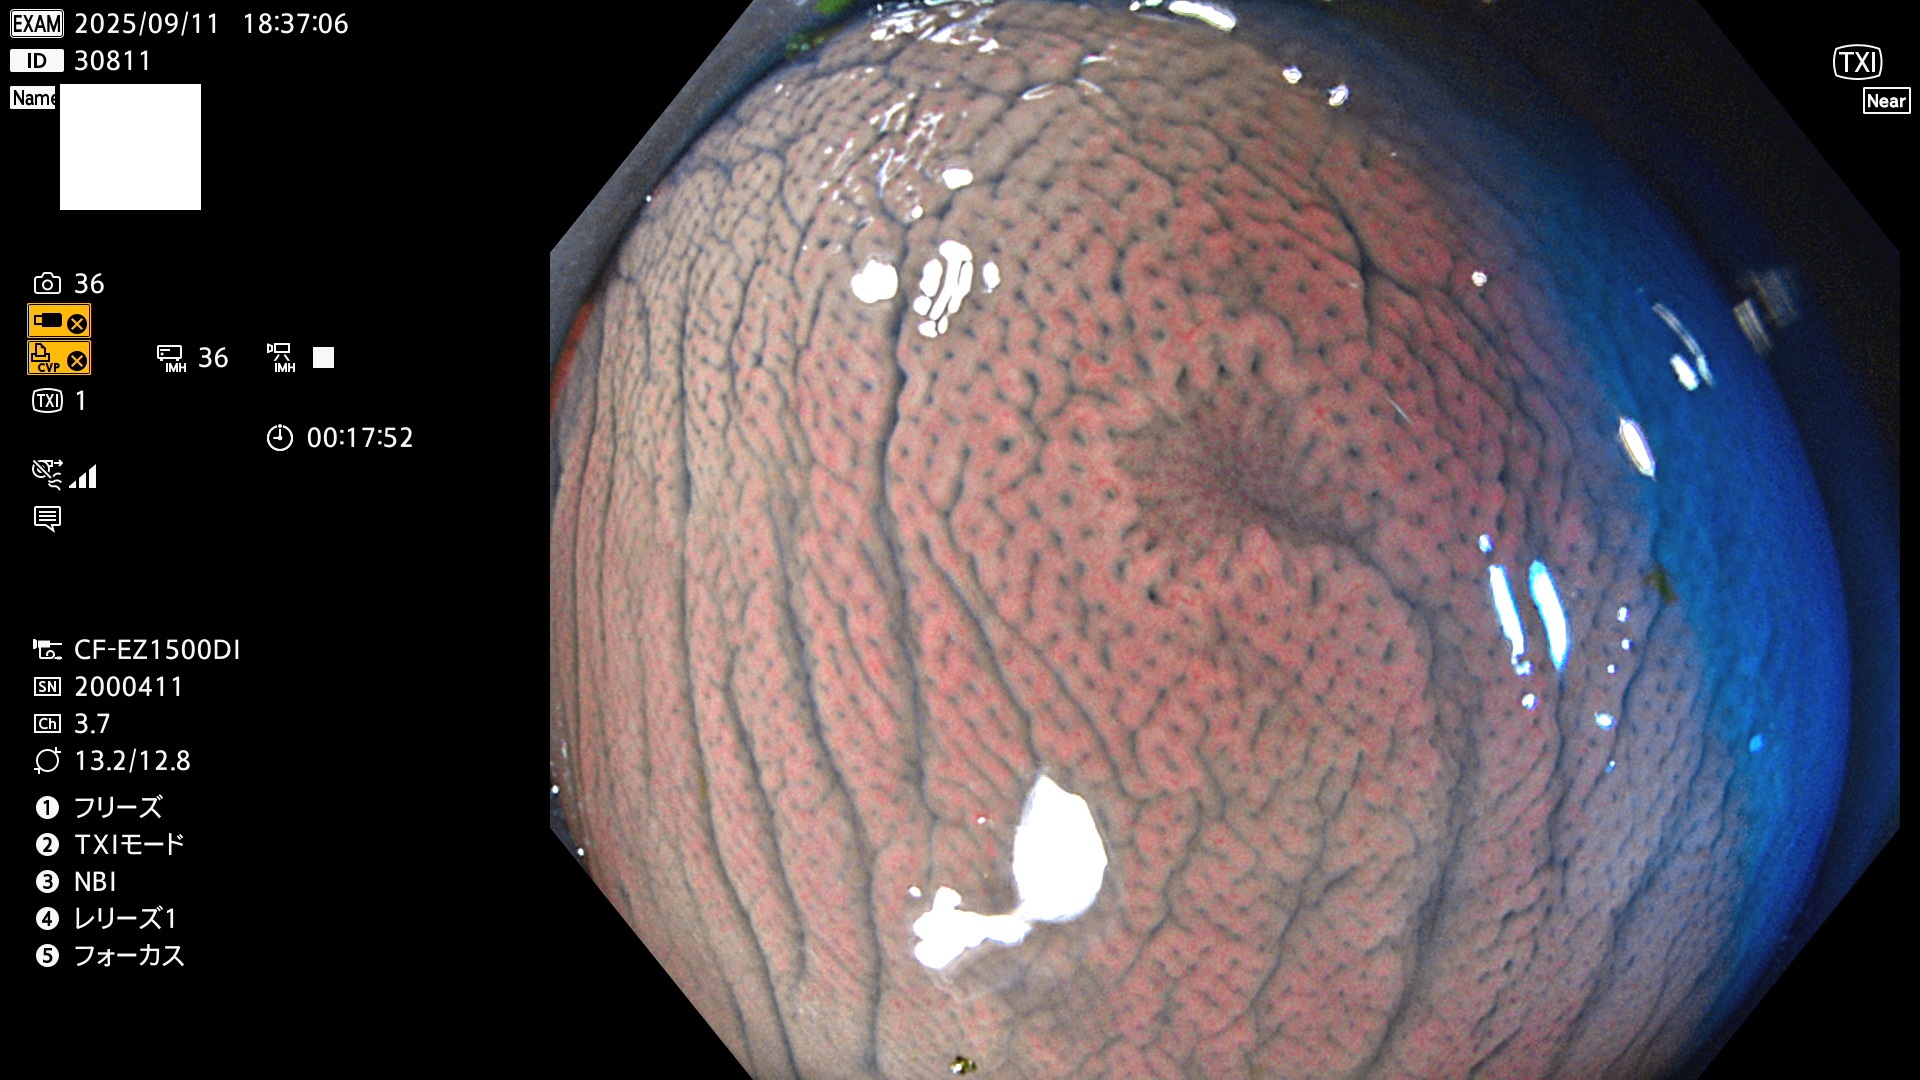

完全に平坦な物をUb、陥凹している物をUcと呼びます。Ubは認識が困難で、Ucはびらん(炎症)と紛らわしいために見落とされやすく、「内視鏡後・大腸癌」の原因になります。

専門的)Uc=De Novo癌? 内視鏡の解像度が低かった時代、このような説もありました。しかし今日の高精度内視鏡では良性の微小なUc型腺腫(APC遺伝子異常の腺腫)が日常的に見つかります。Ucこそが多段階発癌(Adenoma-Carcinoma Sequence)のMain Routeです。

毎週の検査(木・金・土・日)に発見されたUbとUc型・腺腫を、その週の日曜の夜にUPし1週間、提示します。

2025年9月11日〜9月14日の4日間(40件)7個 (Uc_ADR=7個/40人=18%)